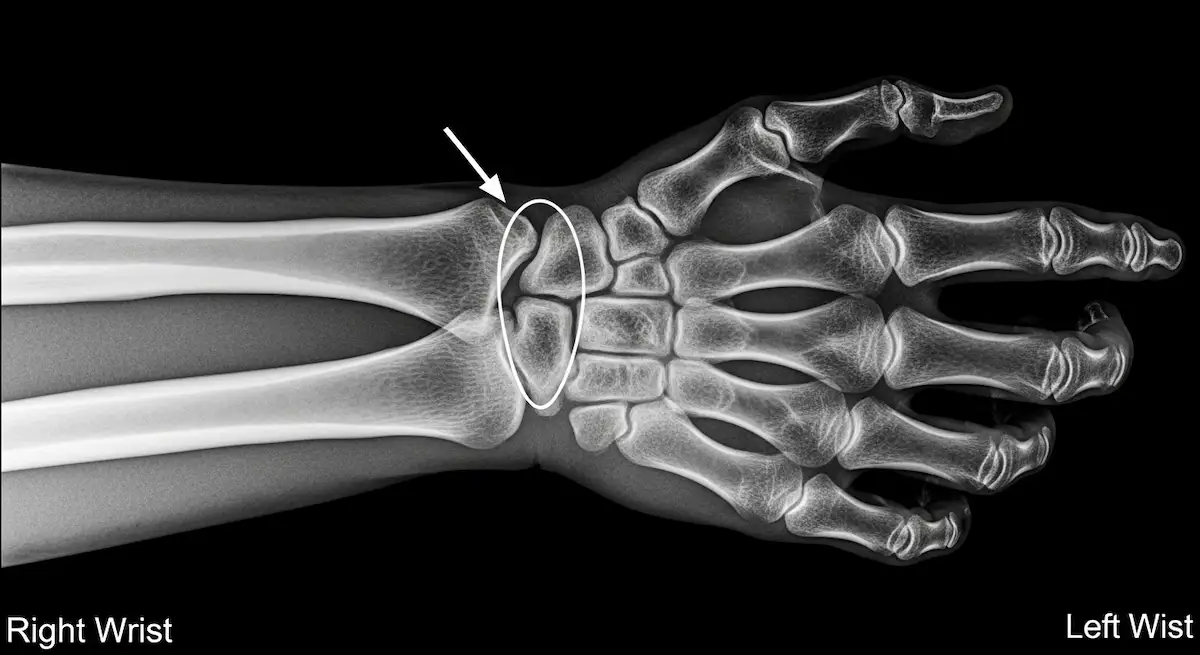

Ao longo de anos de experiência como cirurgião ortopedista especializado em mão, a pseudoartrose do escafoide continua sendo uma das condições mais desafiadoras que encontro em minha prática diária. Esta complicação, que ocorre quando uma fratura do escafoide não consolida…